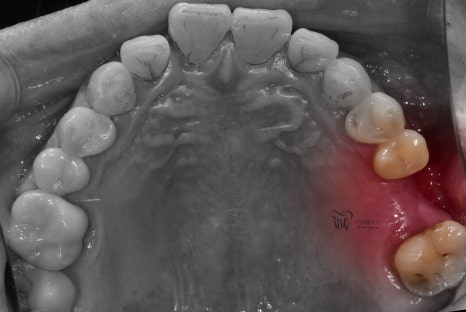

구강내 사진에서도, 아직 잔존 치조골이

충분히 남아있는 것은 확인이 되나

이는 정확히 CT를 찍은 뒤에

네비게이션 임플란트 진단을 해야

정확히 말씀드릴 수 있는 상황이였습니다.